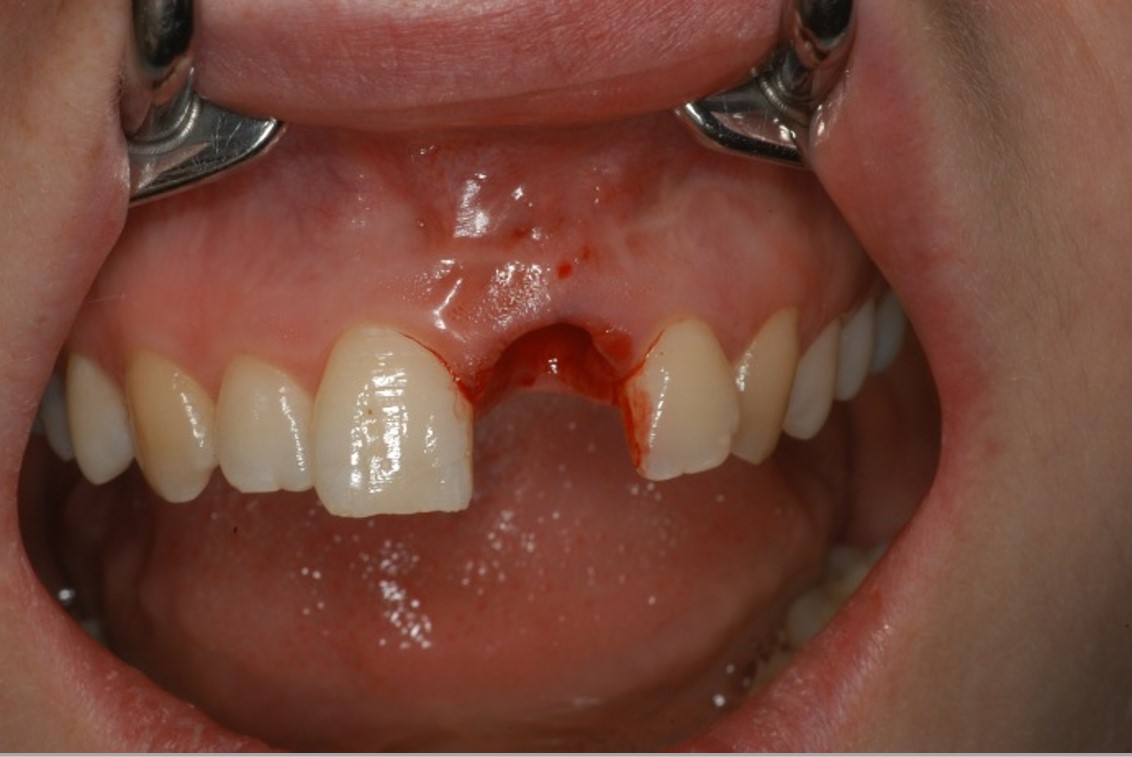

03/12 - Contained defect, boardered by mesiale and distal bone wallTreatment of dehiscence defect with cerabone® & Jason® membrane - Dr. M. Steigmann

04/12 - Implant with extended dehiscence defectTreatment of dehiscence defect with cerabone® & Jason® membrane - Dr. M. Steigmann